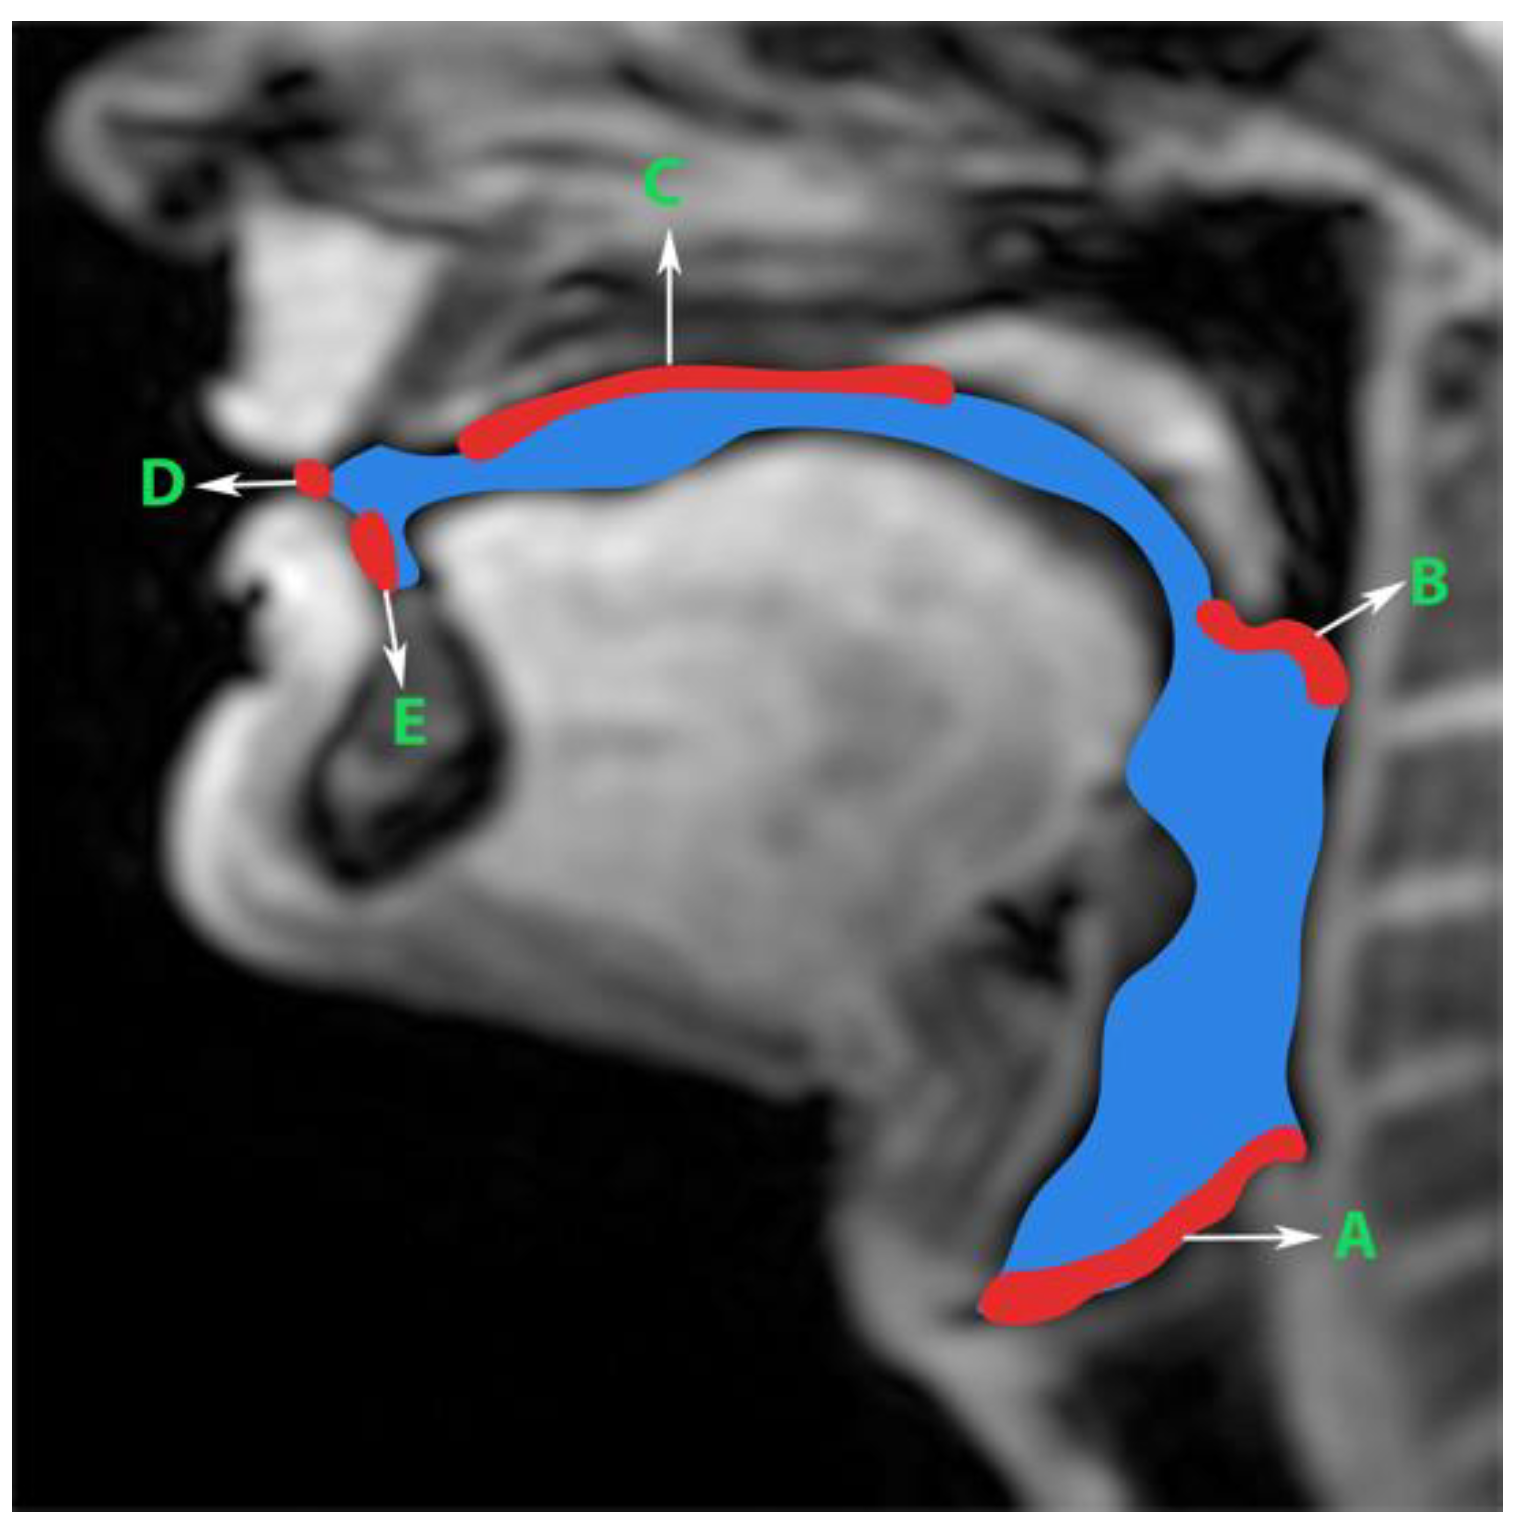

Generation of manual segmentations: To train, validate, and test the STL UNET, we leveraged human annotators to generate manual segmentations. To reduce the subjectivity of test labels, each image in the test set was segmented by three expert humans. The first human annotator was a radiologist with expertise in body, cardiovascular, and thoracic imaging, and with more than 10 years of experience in radiology (author: Priya). The second human annotator was a professional voice user, researcher, and vocologist with more than 20 years of experience in human vocal tract anatomy and voice research (author: Meyer). The third annotator was a graduate student with 4 years of experience in upper-airway MRI and image processing (author: Erattakulangara). Prior to segmentation, all three users established and agreed to an anatomical guide and landmarks to segment the vocal tract (see Figure 2). The three users listed above manually annotated the test set in each of the three protocols by manual pixel-wise labeling of tongue, velum, and airway in either MATLAB R2021 (Mathworks, Natick, MA, USA) or the Slicer platforms (https://www.slicer.org) accessed on 4 August 2022. The third user alone annotated the images in the training and validation sets.

Figure 2. Prior to manual segmentation of the protocol speech MRI datasets, the anatomic boundaries of the vocal tract were established in consensus with all three human annotators: a vocologist, a radiologist, and a biomedical engineer. The blue colored region is the manually segmented upper airway. Red colored regions with notations show the boundaries for creating the manual segmentation. The boundaries are; A—lower boundary (vertebral column 6 and vocal fold), B—inferior boundary of velum, C—hard palate, D—a straight line connecting posterior edge of lower lip with upper lip, and E—region containing teeth up to the soft tissue connecting it.